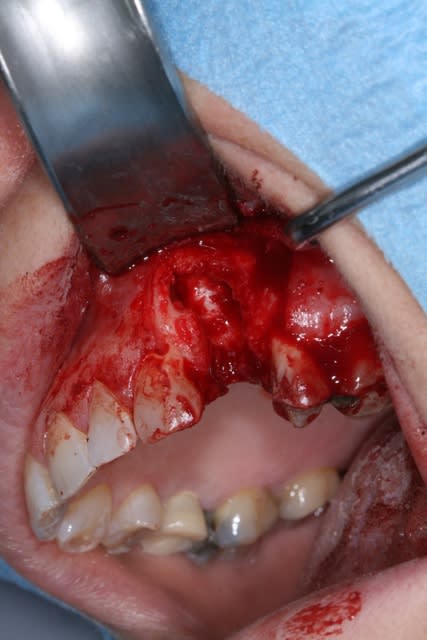

Patiente présente une perte alvéolaire de la table externe suite à fracture radiculaire.

J'ai réalisé un lambeau tracté coronairement mais je pense que certains auraient peut-être réalisé un lambeau conjonctif palatin.

Lambeau lev  qrpmt7 - Eugenol

Alv ole nettoy e fnw3s8 - Eugenol